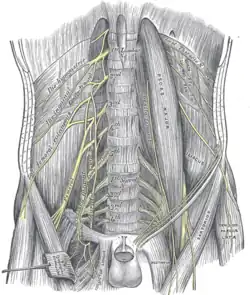

The psoas major and nearby muscles | |

Muscles of the iliac and anterior femoral regions. The lumbar plexus and its branches.

The lumbar plexus and its branches. Psoas major muscle